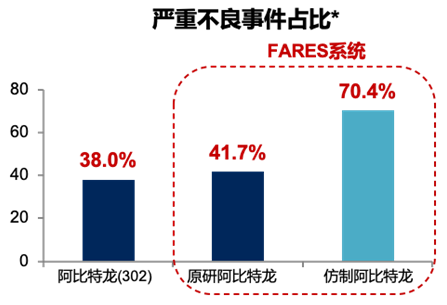

由于原研药价格昂贵,很多患者在选择治疗药物时会选择与其具有生物等效性的仿制药。按照世界卫生组织(WHO)的要求,仿制药的生物利用度在原研药生物利用度的80%~125%之内都认为两者具有生物等效性,但生物等效性在判定原则上会导致两者的生物利用度存在差异,而且会导致仿制药之间的生物利用度差异更大,因此生物等效性≠临床等效性3。

原研醋酸阿比特龙作为进口药,很多患者往往因为价格较为昂贵,无法承担治疗的费用而拒绝用药,退而求其次选择阿比特龙仿制药。尽管仿制药与原研药“形”相似,但“质”存在区别。除循证医学证据外,仿制药与原研药的生产工艺可能存在差异,例如药物中旋光异构体的作用强度和代谢区别会影响药物在体内的过程、作用时间和强度5。而仿制药中工艺杂质的存在也有可能降低药物的疗效,影响药物的稳定性5。